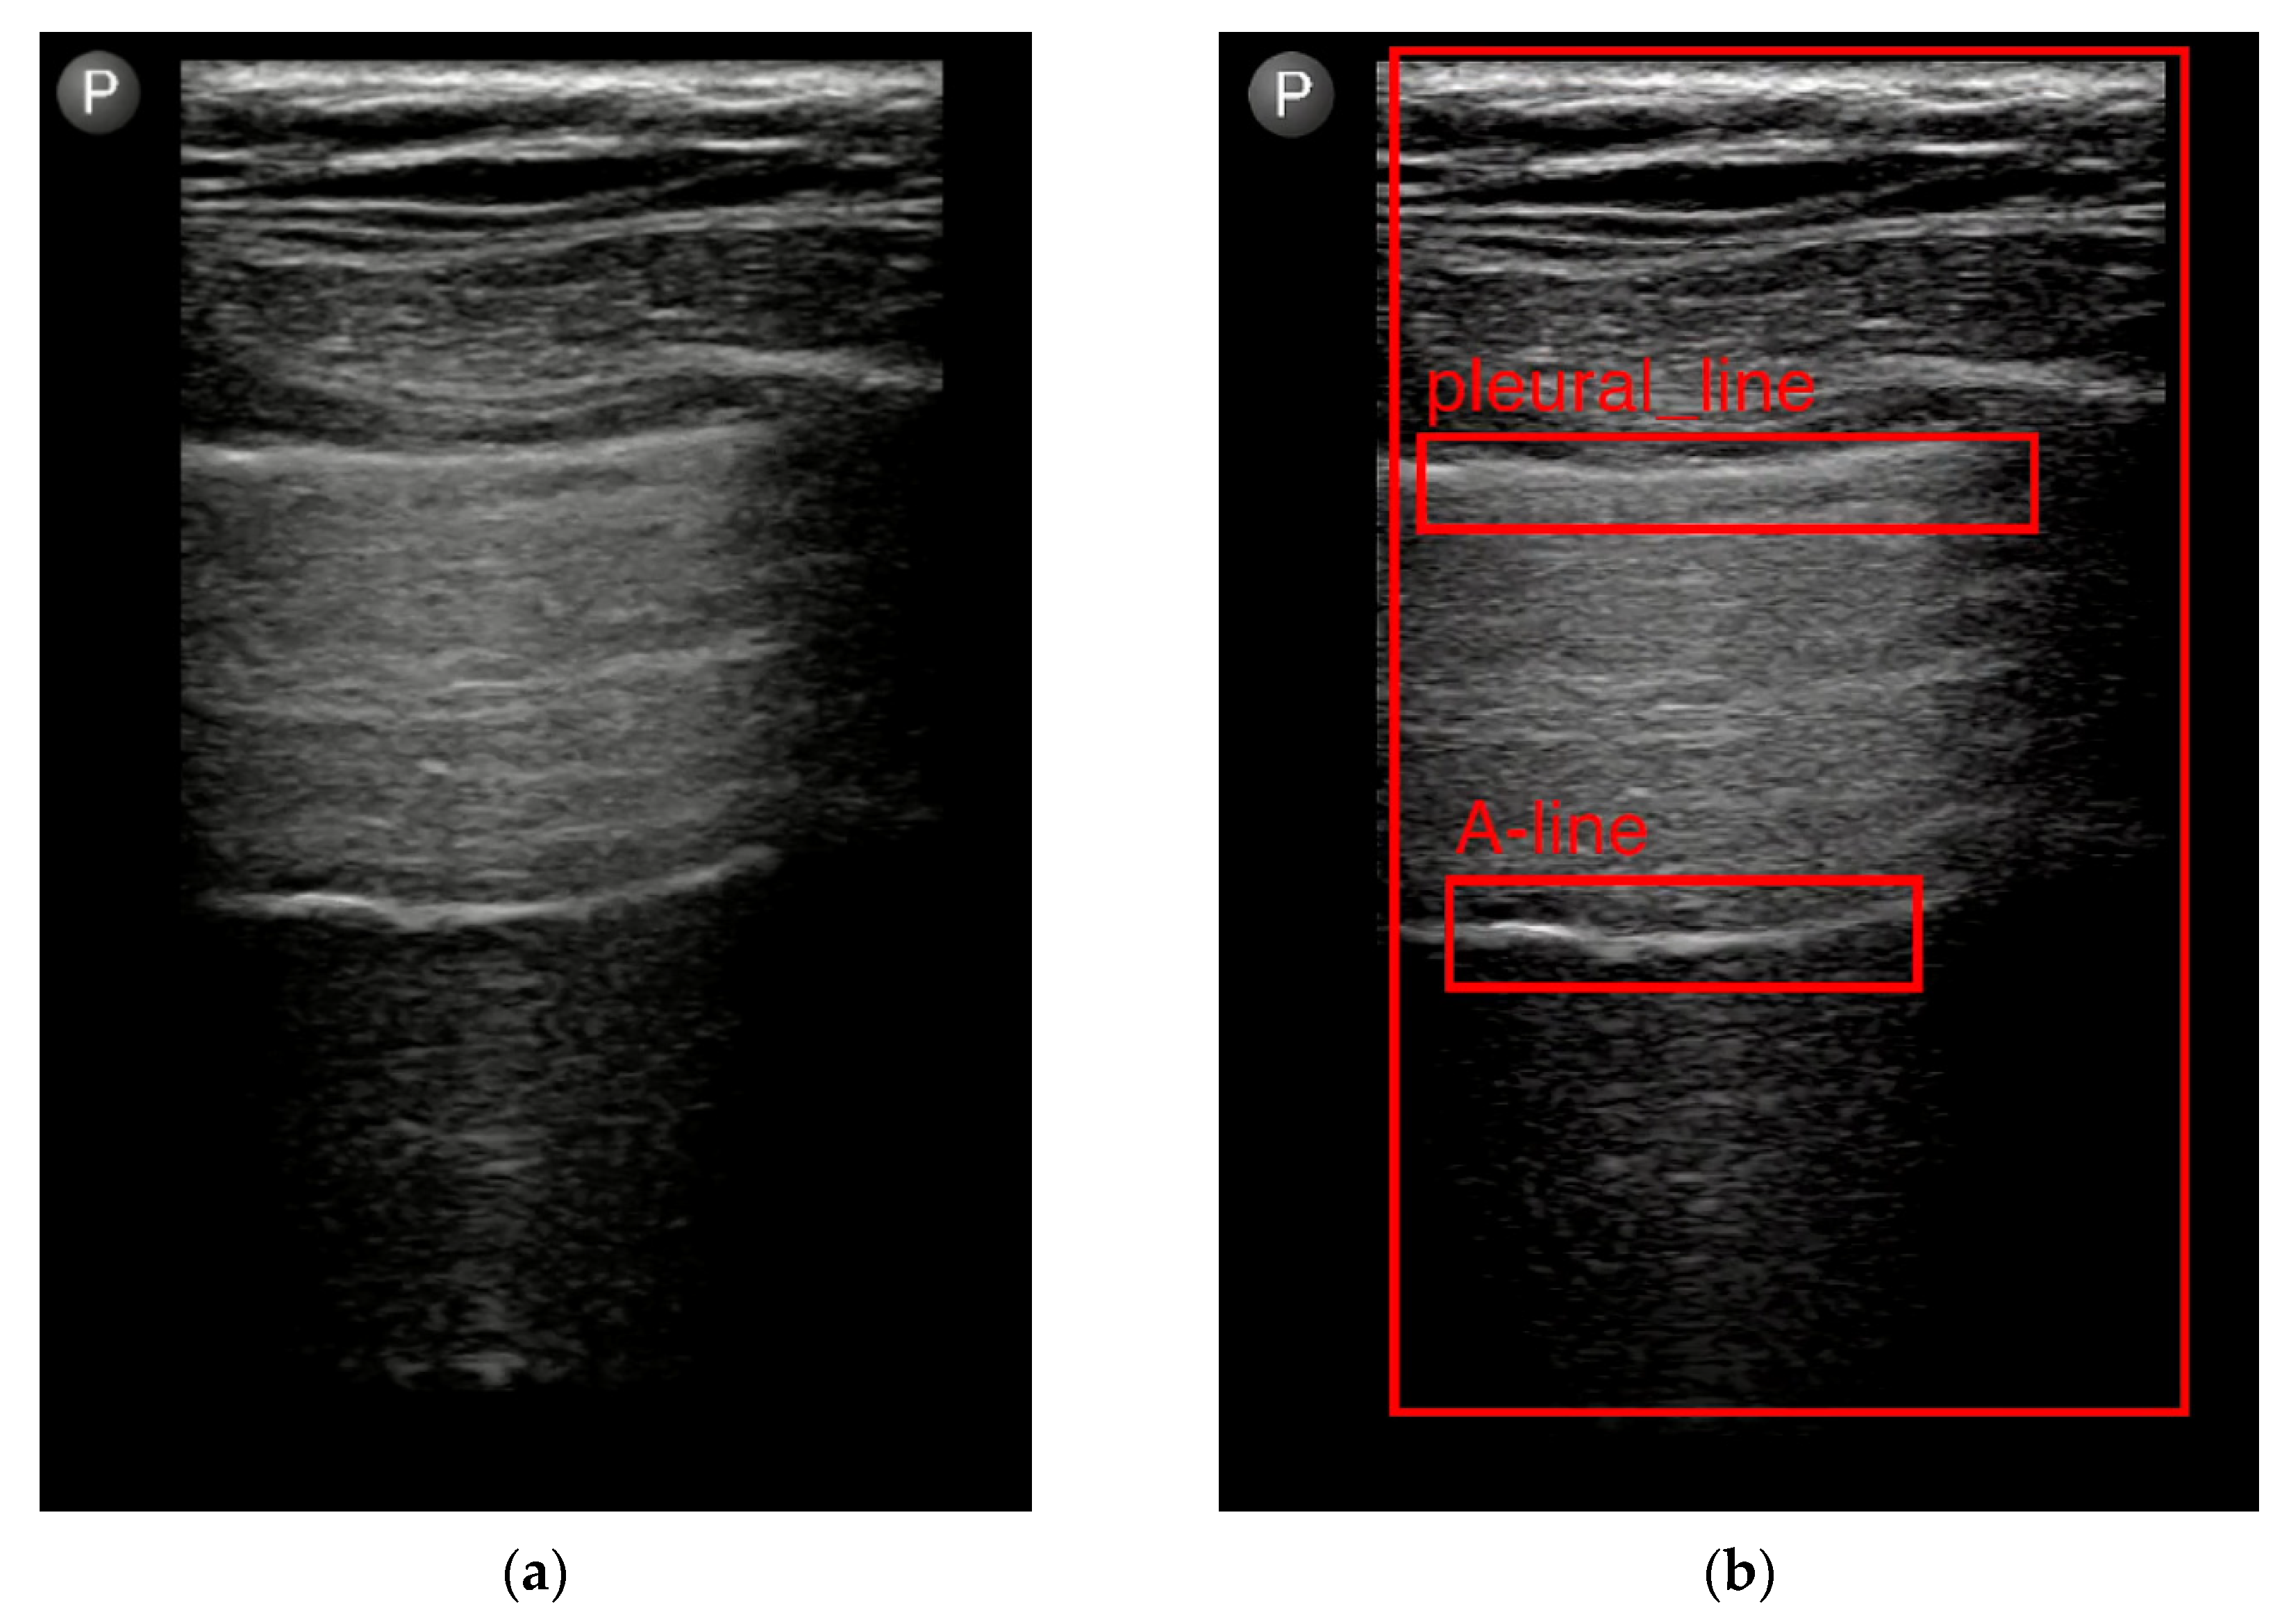

- Jaščur, M.; Bundzel, M.; Malík, M.; Dzian, A.; Ferenčík, N.; Babič, F. Detecting the Absence of Lung Sliding in Lung Ultrasounds Using Deep Learning. Appl. Sci. 2021, 11, 6976. [Google Scholar] [CrossRef]

- Hliboký, M.; Magyar, J.; Bundzel, M.; Malík, M.; Števík, M.; Vetešková, Š.; Dzian, A.; Szabóová, M.; Babič, F. Artifact Detection in Lung Ultrasound: An Analytical Approach. Electronics 2023, 12, 1551. [Google Scholar] [CrossRef]